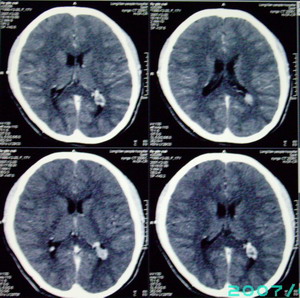

以下是引用九目段在2007-12-24 14:55:00的发言:[br]1,年轻女性[br]2,ct表现:左侧脑室三角区可见一不规则小明显强化的结节,中央见小低密度,侧脑室无扩张。[br]分析:[br]常见的有三种肿瘤好发三角区:[br]1,脉络丛乳头状瘤,好发于年轻者,明显强化,实性,分泌脑脊液,常伴有侧脑室扩大,肿瘤较小可以脑室扩大不明显,不能排除,但小结节尚不易形成坏死腔。[br]2,室管膜瘤,好发于儿童及青少年,明显强化,易坏死,大时伴脑室扩张。[br]3,脑膜瘤,明显强化,圆形,界请,无脑积水,一般不坏死。[br]诊断:[br]左侧脑室三角区结节,考虑室管膜瘤可能性大,不排除脉络丛乳头状瘤和脑膜瘤(因病史较长)。[br][br][本贴已被 九目段 于 2007-12-24 15:13:35 修改过]